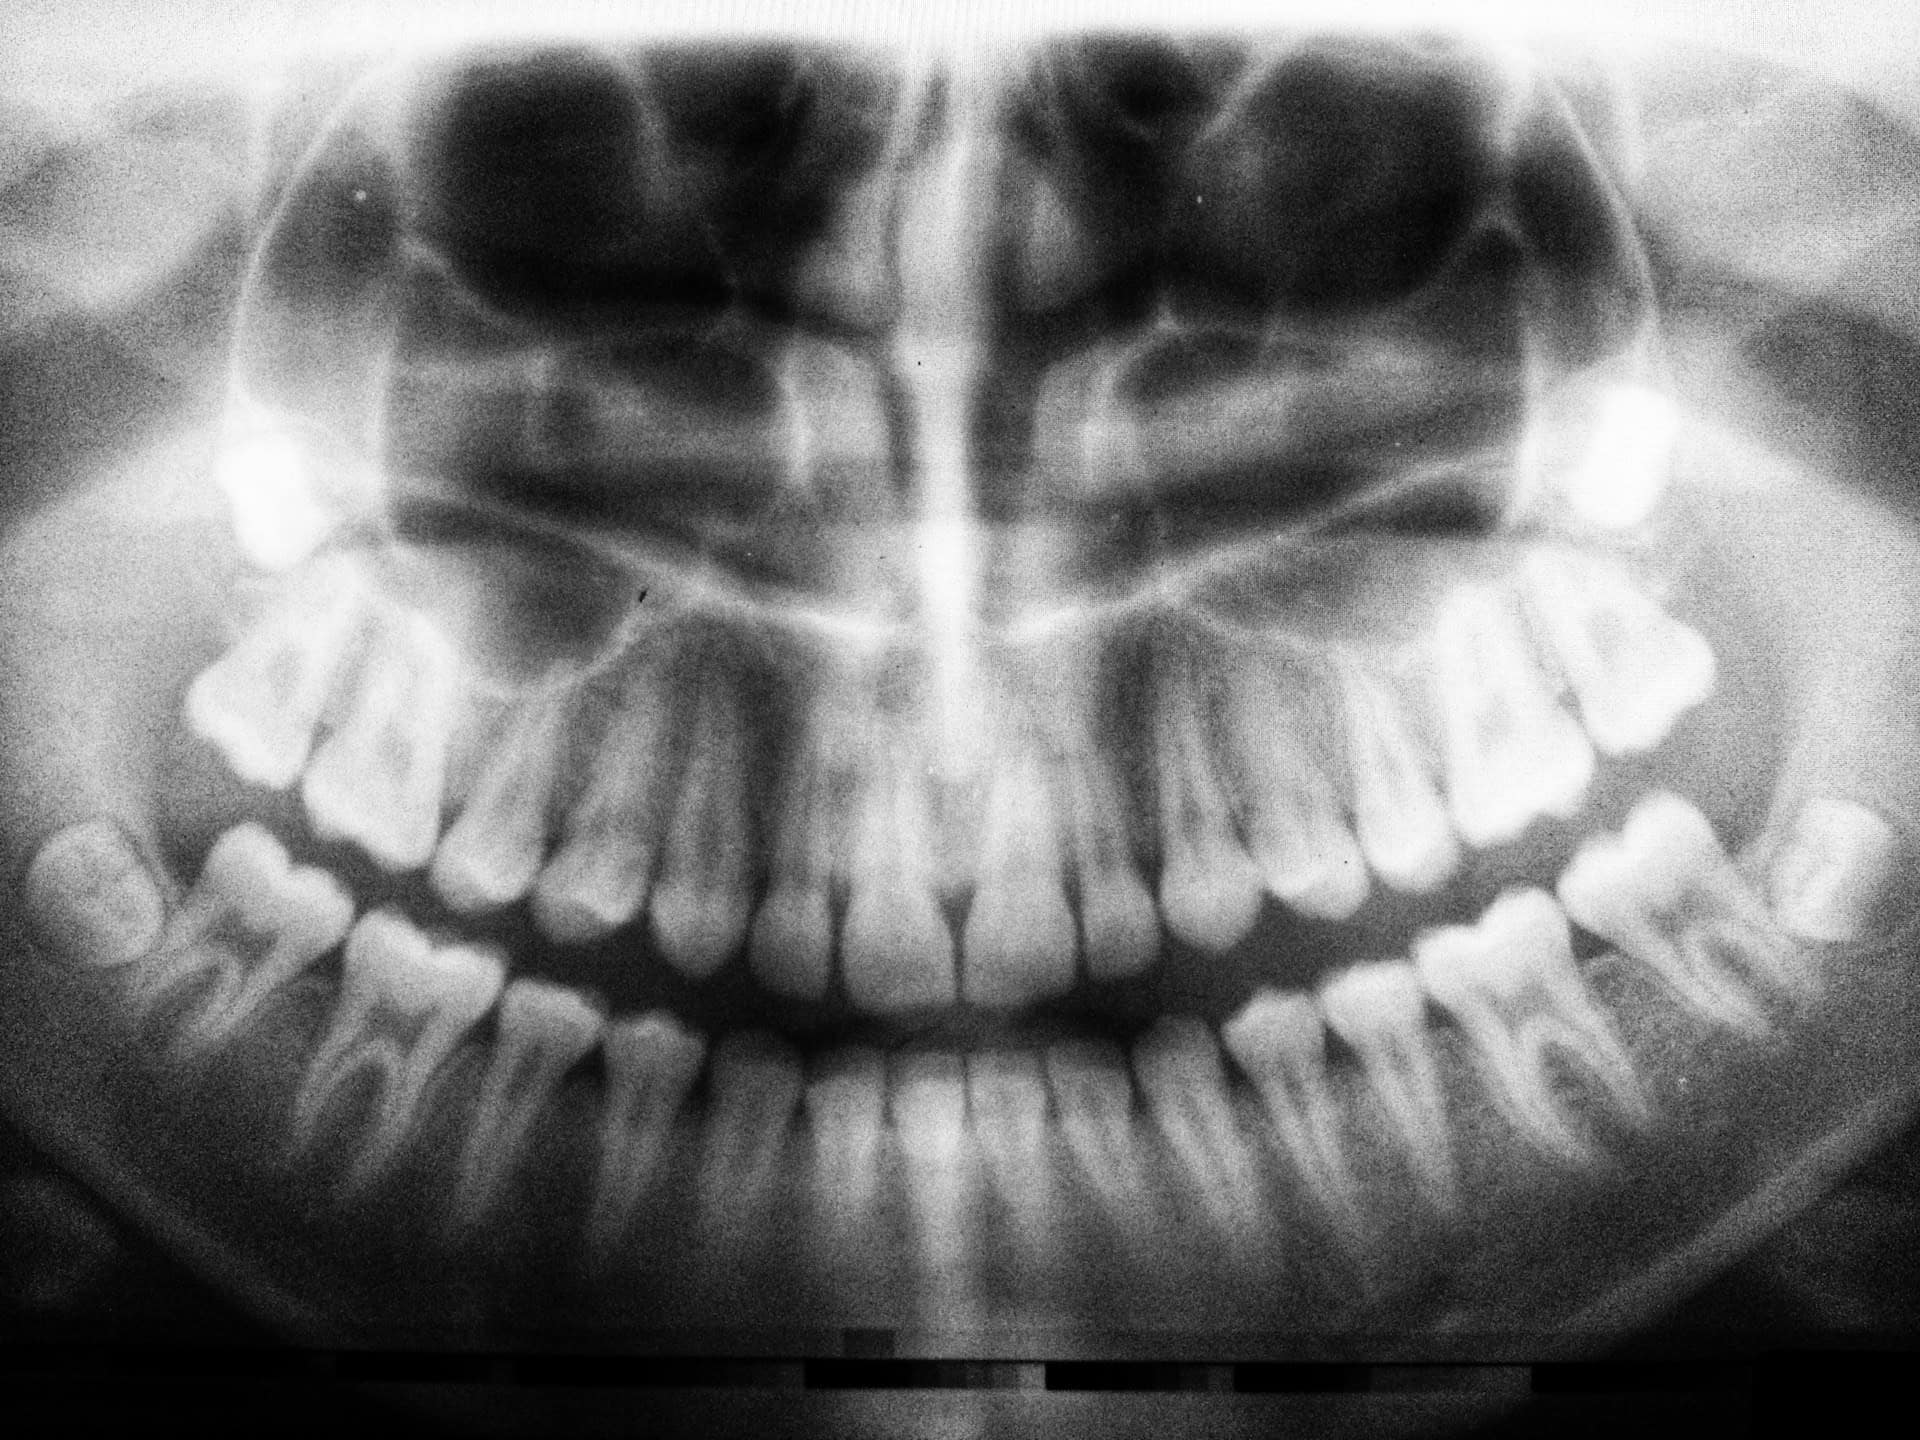

Dental X-rays are a type of imaging technology used to provide a comprehensive view of your oral health that goes beyond what the naked eye can see. They play a critical role in dentistry, offering detailed insights into the health of your teeth, roots, jaw placement, and facial bone composition.

These images are crucial for diagnosing problems such as cavities, tooth decay, impacted teeth, and jawbone damage, which might otherwise remain undetected until they become more severe.

- Panoramic X-rays, which capture an entire image of your oral cavity in a single shot, provide a view that includes your nose, sinuses, jaw joints, and teeth.